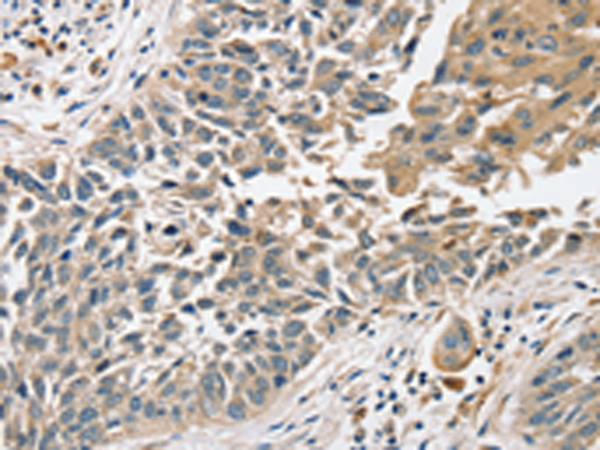

分类: 科研抗体货号: P12180别名: CJMG; MCT12应用: IHC反应种属: Human